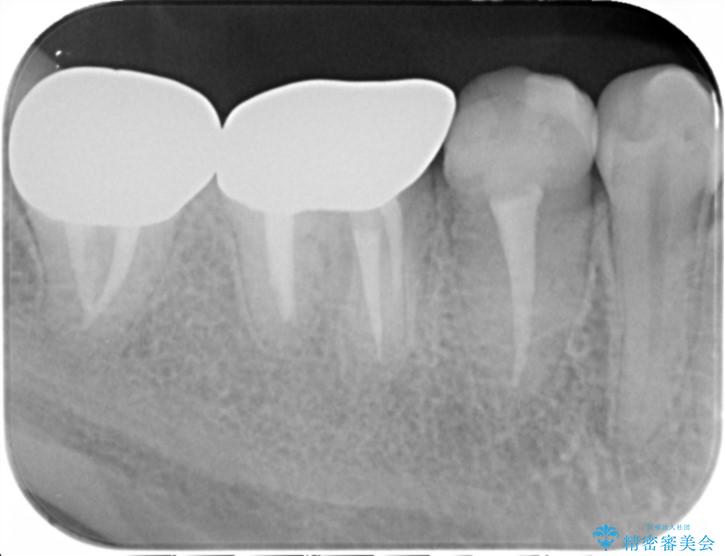

奥歯は既に根管治療が為されクラウンを装着する必要性がある状態ですが、歯の高さが低くクラウンの安定性・強度を担保するために歯周外科を行う治療計画としました。

歯周外科を行うことで、歯ぐきの位置を下げ歯の高さを作り出し安定したクラウンの装着が可能となります。また同時に舌の邪魔となっていた骨隆起の除去を行うこととしました。